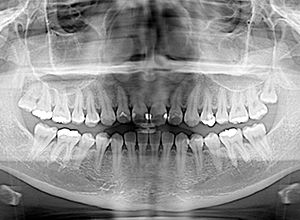

X-Ray

X-Ray所見

セファロ所見 下顎頭はやや後方に位置しているが、下顎は大きく力強い形態をしており下顎角は平均的であるのに対して、中顔面部は奥行きがなく前後的には後方に位置づいており劣位であるため、下顔面高は低く垂直的にはShort face様骨格形態を呈していた。

パノラマ所見 上顎両側8が存在していた。下顎臼歯は近心傾斜が認められた。